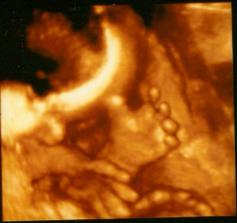

27. týden těhotenství - opět vidíme holčičku, máme za sebou 3D ultrazvuk....